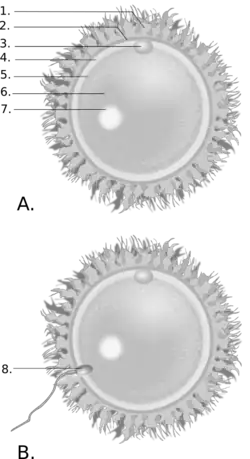

1. corona radiata; 2.zona pellucida; 3. polární tělísko; 4. perivitellinní prostor; 5. cytoplazmatická membrána (oolemma); 6. cytoplazma; 7. jádro;

B – oplodnění

8. spermie

Biologie oplodnění

Koitus je základní reprodukční metoda druhu Homo sapiens, stejně jako savců. Během ejakulace, která obyčejně provází mužský orgasmus, série svalových stahů (kontrakcí) dopraví semeno obsahující mužské gamety nazývané spermiové buňky nebo spermie do pochvy. Následuje cesta spermií z pochvy přes děložní hrdlo (cervix) do dělohy a odtud do vejcovodů. Spermiové buňky mohou přežít v ženském těle 2–3 dny, podle některých autorů i více.[14][15][16] Když se plodné ženské vajíčko nachází ve vejcovodech, spermie do něj pronikne a způsobí oplodnění (fertilizaci) a formaci nového embrya. Když oplodněné vajíčko dosáhne dělohy, zahnízdí se v děložní výstelce nazývané endometrium a začne těhotenství.